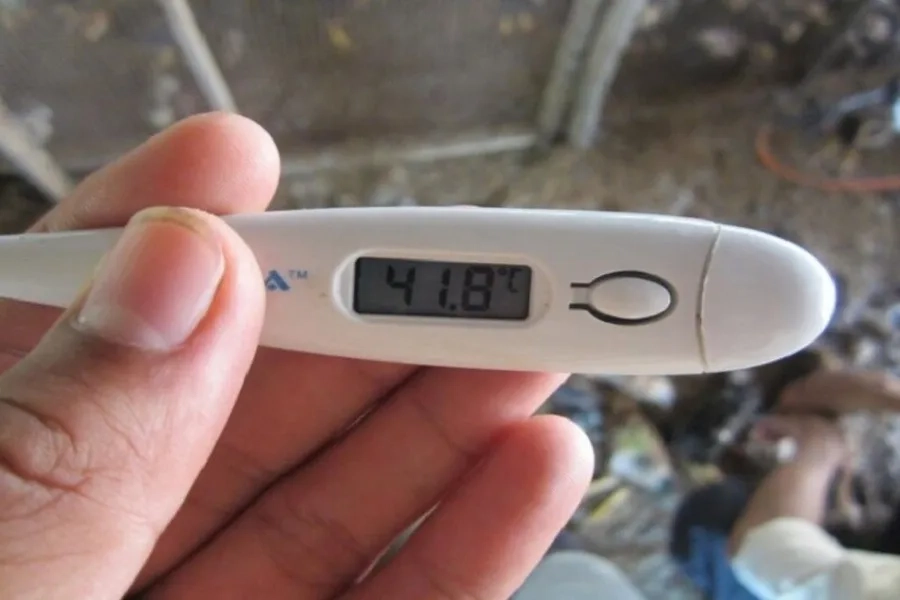

Triệu chứng bệnh sốt xuất huyết ở giai đoạn đầu nổi bật nhất là sốt cao đột ngột, nhiệt độ có thể lên tới 39-40°C. Cơn sốt thường kéo dài từ 4-7 ngày và ít đáp ứng với thuốc hạ sốt thông thường.

Sốt cao không hạ là biểu hiện sốt xuất huyết dễ dàng nhận thấy đầu tiên